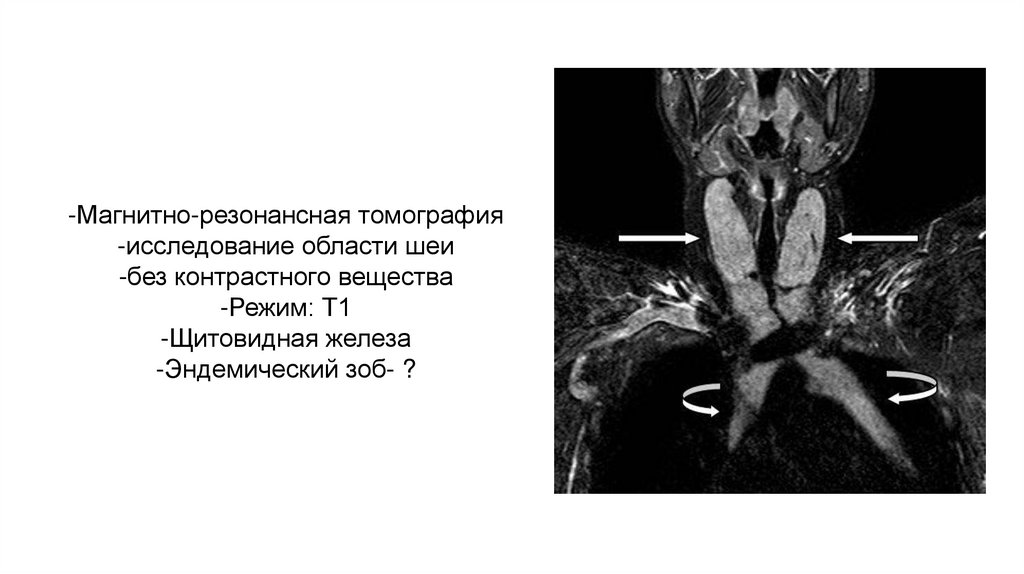

-Магнитно-резонансная томография

-исследование области шеи

-без контрастного вещества

-Режим: Т1

-Щитовидная железа

-Эндемический зоб- ?